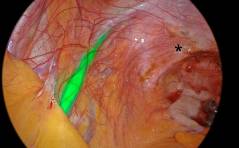

Tipps und Tricks

Nie mehr suchen! ICG-Darstellung der Ureteren bei tiefinfiltrierender Endometriose und anderen komplexen laparoskopischen Eingriffen PDF DokumentSonoquiz: Was ist Das?